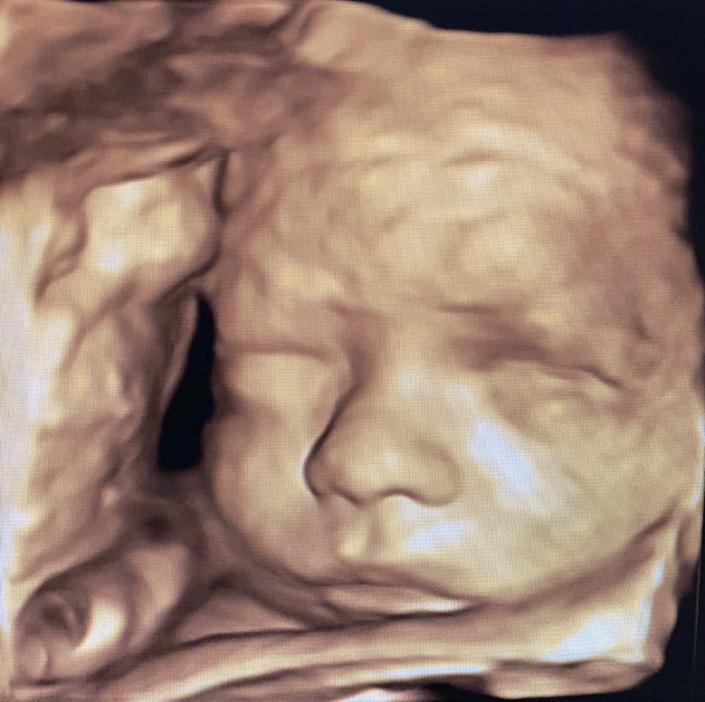

Prenatal Peek®

Prenatal Peek is the leader in 3D 4D Ultrasound. We employ only Certified / Registered Sonographers maintaining unsurpassed standards in 3D ultrasound. You deserve the best! Call us today.